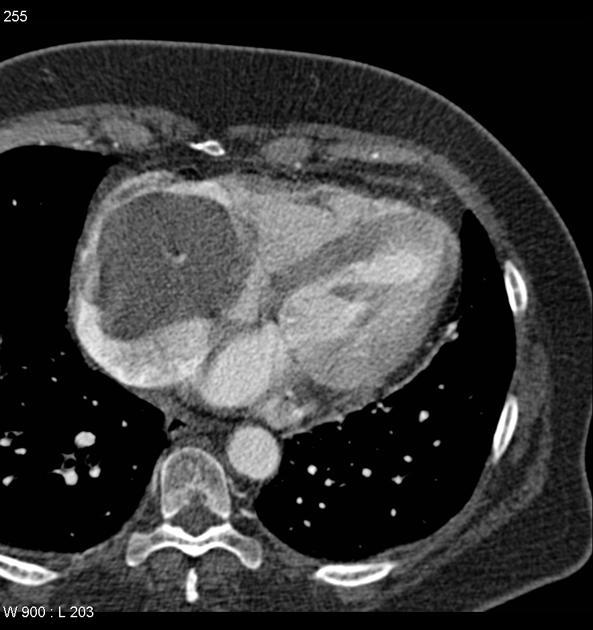

CT

CT is most commonly used for imaging assessment of mesothelioma, and sufficient for accurate staging of disease in most patients.

pleural mass or nodular thickening of soft tissue attenuation

tends to cause “inward” contraction of the hemithorax, e.g. ipsilateral mediastinal shift

pattern of spreadpattern of spread initially to adjacent pleura

involvement pleural fissures

eventually grows toward lung encasement (“pleural rind’)

predilection for local invasion

involvement of chest wall, diaphragm, and mediastinal content typical 1,2,4

chest wall involvement

infiltration of the extra-pleural fat plane 4

obvious direct extension in bone or muscle 4

known to invade along prior catheter and biopsy tracks 18

pericardial effusion may suggest transpericardial extension 3,4

frequent metastasis to local lymph nodes and contralateral lung

calcification

seen in 20% - usually represents engulfment of calcified pleural plaques rather than true tumor calcification 4

sarcomatoid variants may contain calcific osteosarcoma or chondrosarcomatous components